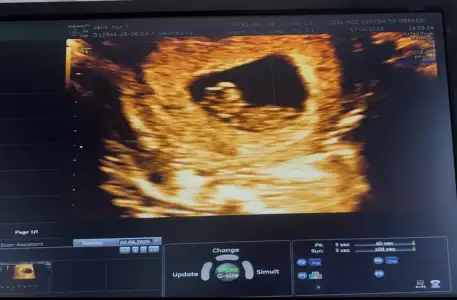

Kızlar benim bebişim de 9+0 da 😍 kese önceli haftalarsa yusyuvarlaktı şimdi şekli değişmiş. Doktor kız gibi tahmin ediyorum dedi. Sizde hislerinizi söyler misiniz 😍

• IMG_8815.webp

IMG_8815.webp

27,5 KB · Görüntüleme: 66